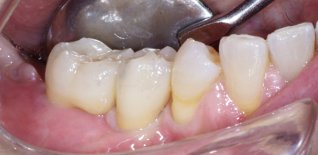

Successivamente sono stati applicati degli elementi dentari.